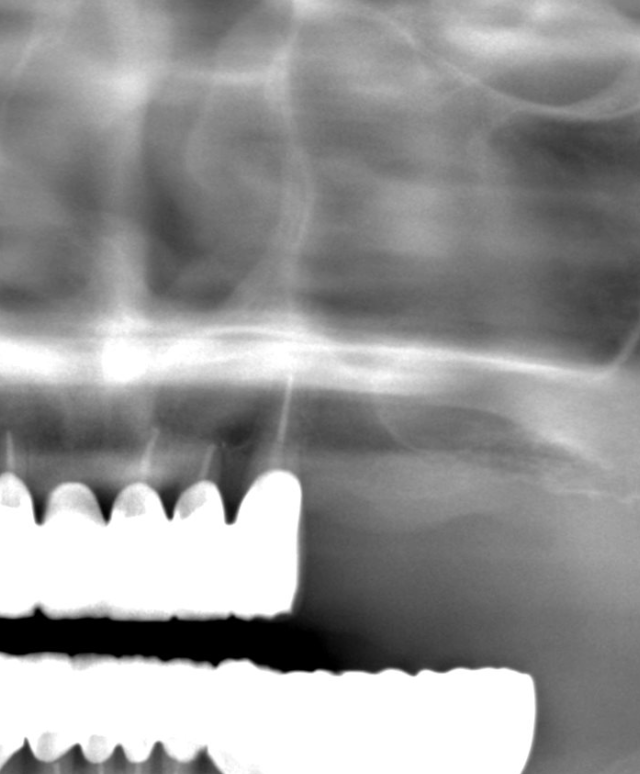

処置前のレントゲンです。

上の奥歯に歯がないのが分かると思います。

通常のレントゲンだけだと正確な診断ができないためCTを撮影します。